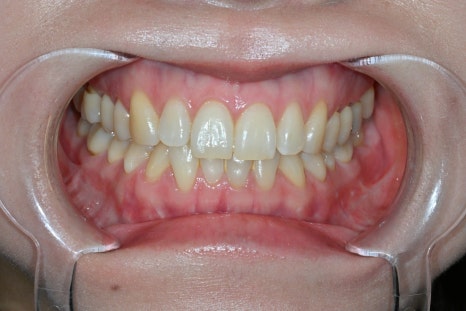

Changes after treatment

<BEFORE>

<AFTER>

After treatment, the patient experienced

a natural smile

a softer change in impression

greater satisfaction in photos

In particular, there were many comments like

"I can't tell that they had laminates"

"It just feels like they became prettier."

This is exactly the result of

Obzero Pure Laminates.